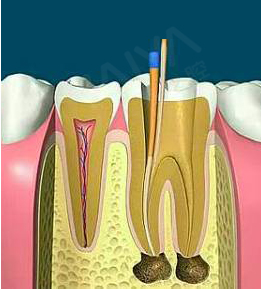

通过机械和化学方法去除根管内的大部分感染物,并通过充填根管、封闭冠部,防止发生根尖周病变或促进已经发生的根尖周病变的愈合。

适应症:牙根尖周炎